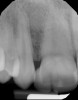

A 9-year-old girl, referred to a prosthodontic office by her pediatric dentist, presented with her mother’s chief complaint: “The kids are teasing her about her big front tooth.” Findings from radiographic and clinical examinations revealed fused maxillary central-peg lateral incisors, teeth Nos. 7 and 8, and a congenitally missing lateral incisor, tooth No. 10 (Figure 1 through Figure 3). An implant was selected as the ideal treatment to replace tooth No. 10 when somatic growth was complete. A diagnostic wax-up was fabricated to determine if the fused tooth could be made to resemble two teeth, using pink composite to give the illusion of an interproximal papilla. The patient was referred for an orthodontic consultation to plan for closure of the diastema between teeth Nos. 8 and 9 and achievement of proper alignment for implant No. 10. The patient was also referred to a periodontist for pretreatment assessment of the tooth No. 10 site. An endodontist was consulted should exposure of the large pulp occur during tooth preparation.

Fig 3. Radiographic scan of fused maxillary central-peg lateral incisors, teeth Nos. 7 and 8, and congenitally missing lateral incisor, tooth No. 10.

Figure 3